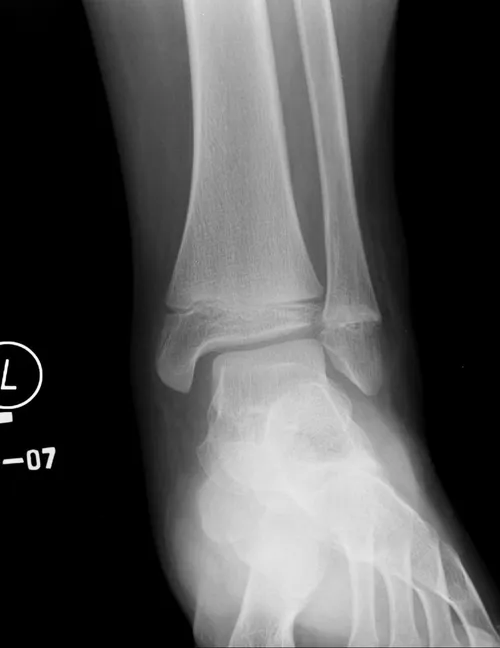

Salter-Harris I fracture is a complete separation of the epiphysis from the metaphysis with the fracture line passing through the physics. This injury is more common in young children. In most cases, there is a spontaneous reduction of the fracture. Treatment includes below knee cast or CAM walker immobilization.